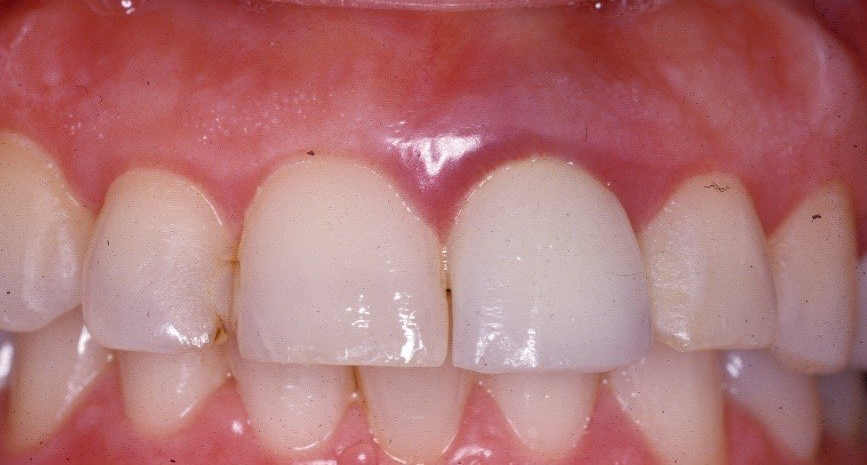

Il sorriso di un Toronto Bridge (6)